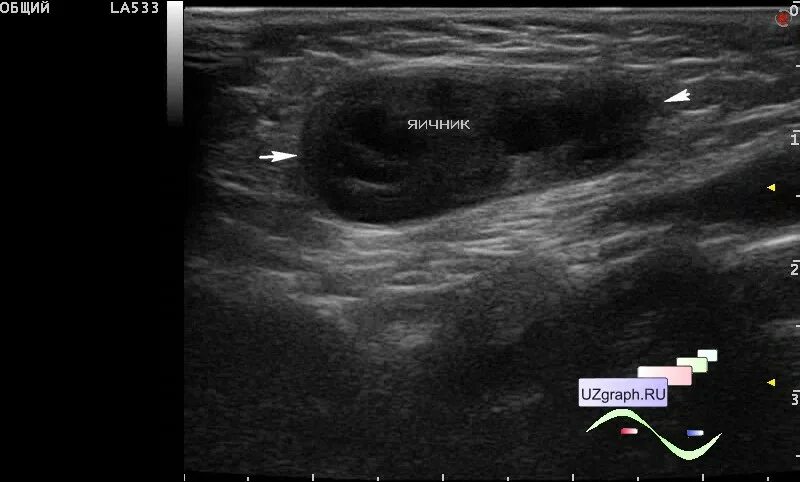

Симптомы мошоночной грыжи